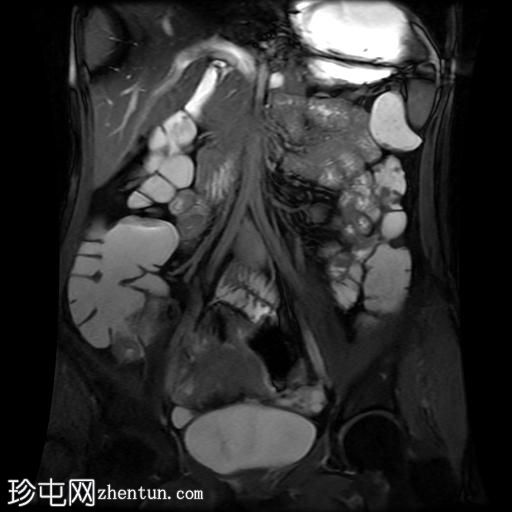

冠状位T2加权像

脂肪抑制

回肠末端及盆腔回肠肠袢可见长段肠壁增厚及强化,肠周血管丰富,呈“梳状征”,并可见明显的纤维脂肪浸润。

未见瘘管、积液、腹水或梗阻。

磁共振肠道造影(MRE)结果支持克罗恩病的诊断,显示远端及末端回肠以活动

性病

变为主,并可见明显的肠周血管。